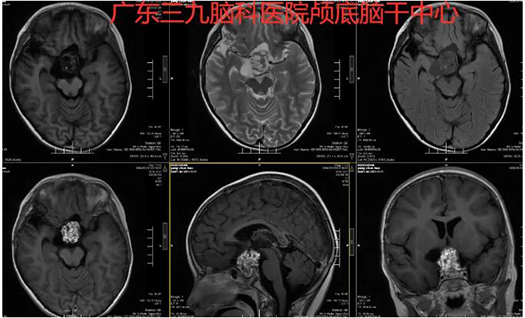

图2:术前MR示右侧颞叶示斑片状长T1长T2异常信号影,FLAIR序列呈内低外高信号,邻近脑沟稍增宽。鞍区示一囊实性占位性病变,实性部分呈不均匀等、长T1等、长T2异常信号影,FLAIR序列呈稍低信号,囊性部分呈长T1长T2异常信号影,FLAIR序列呈低信号,增强后实性部分呈明显不均匀异常强化影,囊性部分未见强化,大小约为4.3cm×3.9cm×3.9cm,垂体及垂体柄、视交叉受压显示不清,病变紧贴双侧大脑前中动脉起始部,双侧大脑前动脉A1段受压移位。

图3:术前术后MR示右侧额部呈术后改变,原鞍区病变已切除。